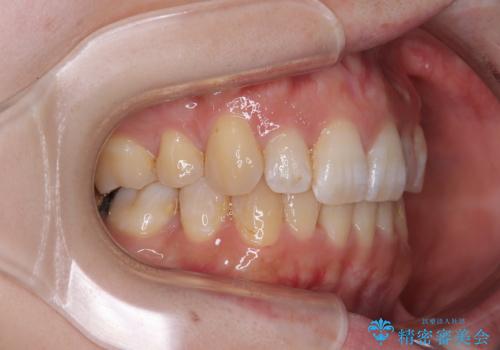

非抜歯矯正にて治療を行うと、仕上がりで口元が突出する可能性があったため、小臼歯抜歯での矯正治療を行うこととしました。

上顎は左右の第一小臼歯2本を、下顎は左右の第二小臼歯2本を抜歯して、口元が突出しないようにしながら、奥歯の咬み合わせを改善していく治療計画としました。

第二小臼歯抜歯としたため、治療期間は長くなりましたが、満足のいく仕上がりとなりました。